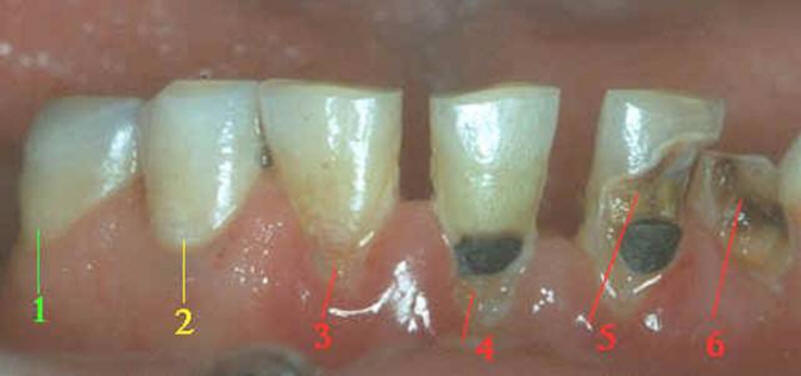

ASPECTO VISUAL: Cuando se ve húmeda no hay evidencia de

cambio en el color atribuibles a la actividad de caries, pero después

del secado con aire por 5 segundos, una opacidad de caries o cambio de

color (mancha blanca o lesión marrón) es visible, lo cual no es consistente con

la apariencia clínica del esmalte sano, el cambio de color se

limita al fondo de la fosa o fisura.

La desmineralización progresa,

aumentando el tamaño y el número de poros en la sub-superficie.

La capa superficial del esmalte se

encuentra intacta con poca pérdida mineral. No hay

invasión bactriana en la sub-superficie ni tampoco se ha

formado una cavidad. La mancha blanca es observada

en esmalte húmedo.

ASPECTO VISUAL:

Al observar el

diente en estado húmedo verá una decoloración (mancha blanca

/ marrón)

en el fondo de la fosa y fisura, que desborda hacia las

paredes. (mas ancha que la fosa y fisura) las manchas

no tienen brillo y es consistente con desmineralización.

Lesión

incipiente en progreso (activa):

-

La superficie del

esmalte es blanquecina / amarillenta.

Es opaca con pérdida

de brillo; se siente áspero cuando se mueve

la punta de la sonda suavemente a través de

la superficie.

La lesión está en un

área de estancamiento de placa madura, es

decir: en fosas y fisuras, cerca del margen

gingival y superficie proximal, por debajo

del punto contacto.

Si esta cerca del la

encía, esta suele sangrar.

Lesión de

caries incipiente detenida:

esmalte es blanquecina, marrón o negra.

El esmalte se observa

con brillo y puede ser suave cuando se mueve

la punta de la sonda a través de la

superficie.

En las superficies

lisas libres, la lesión de caries suele

estar situada a cierta distancia de la

margen gingival.

No suele haber placa

madura ni sangrado del margen gingival.